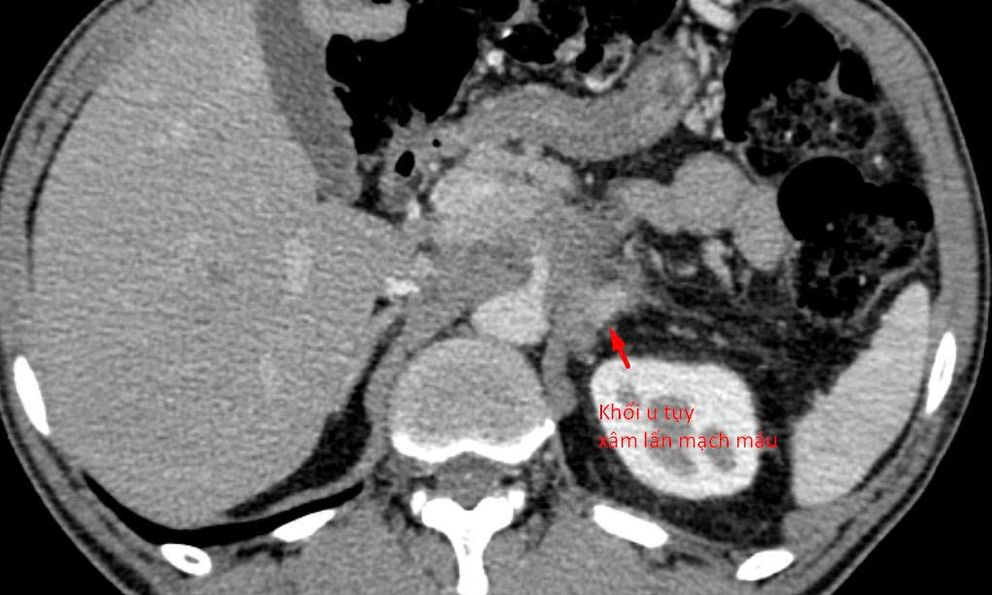

Bệnh nhân 64 tuổi (tại Hà Nội) có khối u tụy xâm lấn mạch máu được chẩn đoán tại nhiều bệnh viện khác nhau. Tuy nhiên, do khối u nằm ở vị trí đặc biệt phức tạp, áp sát nhiều cấu trúc nguy hiểm, các bác sĩ chưa thể tiến hành sinh thiết để xác định mô bệnh học – bước then chốt quyết định hướng điều trị ung thư.

Sau khi tiếp nhận bệnh nhân, các bác sĩ đã tiến hành đánh giá lại toàn bộ cấu trúc giải phẫu và đường tiếp cận khối u. Hầu hết các hướng sinh thiết thông thường đều không khả thi do nguy cơ tổn thương mạch máu lớn và các tạng quan trọng.

“Chúng tôi chỉ còn một ‘khe cửa hẹp’ duy nhất: tiếp cận từ phía sau, xuyên qua khoảng giữa cột sống và thận. Đây là đường vào rất khó, rủi ro cao và đòi hỏi kỹ thuật can thiệp cực kỳ tinh vi”, bác sĩ Giang chia sẻ.

Dưới hướng dẫn của CT đa dãy độ phân giải cao, mũi kim sinh thiết được đưa chính xác qua khe an toàn duy nhất, tiếp cận khối u và lấy mẫu bệnh phẩm thành công. Thủ thuật diễn ra an toàn, không ghi nhận biến chứng, mẫu mô đạt yêu cầu để phục vụ chẩn đoán.